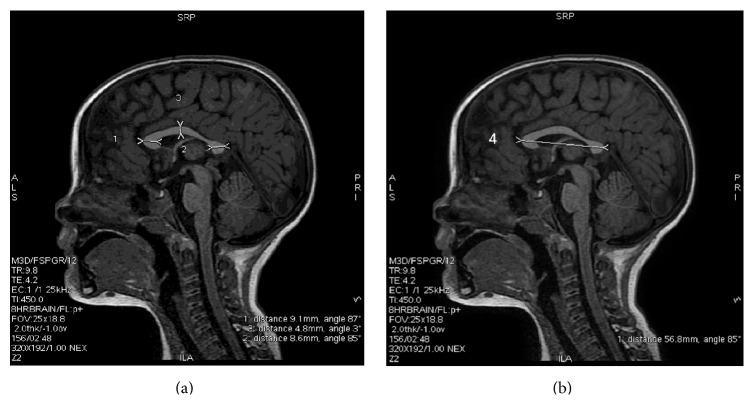

To assess the relationship between stereoscopic vision, visual perception, and microstructure of the corpus callosum (CC) and occipital white matter, 61 children born with a mean birth weight of 1024 g (SD 270 g) were subjected to detailed ophthalmologic evaluation, Developmental Test of Visual Perception (DTVP-3), and diffusion tensor imaging (DTI) at the age of 4.

Abnormal stereoscopic vision was detected in 16 children. Children with abnormal stereoscopic vision had smaller CC (CC length: 53 ± 6 mm versus 61 ± 4 mm; p < 0.01; estimated CC area: 314 ± 106 mm(2) versus 446 ± 79 mm(2); p < 0.01) and lower fractional anisotropy (FA) values in CC (FA value of rostrum/genu: 0.7 ± 0.09 versus 0.79 ± 0.07; p < 0.01; FA value of CC body: 0.74 ± 0.13 versus 0.82 ± 0.09; p = 0.03). We found a significant correlation between DTVP-3 scores, CC size, and FA values in rostrum and body. This correlation was unrelated to retinopathy of prematurity.

为评估立体视觉、视觉感知与胼胝体(CC)及枕叶白质微观结构之间的关系,对61名平均出生体重为1024克(标准差270克)的儿童在4岁时进行了详细的眼科评估、视觉感知发育测试(DTVP - 3)和扩散张量成像(DTI)。

16名儿童检测出立体视觉异常。立体视觉异常的儿童胼胝体较小(胼胝体长度:53±6毫米对61±4毫米;p<0.01;估计胼胝体面积:314±106平方毫米对446±79平方毫米;p<0.01),胼胝体的分数各向异性(FA)值较低(喙部/膝部的FA值:0.7±0.09对0.79±0.07;p<0.01;胼胝体体部的FA值:0.74±0.13对0.82±0.09;p = 0.03)。我们发现DTVP - 3得分、胼胝体大小与喙部和体部的FA值之间存在显著相关性。这种相关性与早产儿视网膜病变无关。